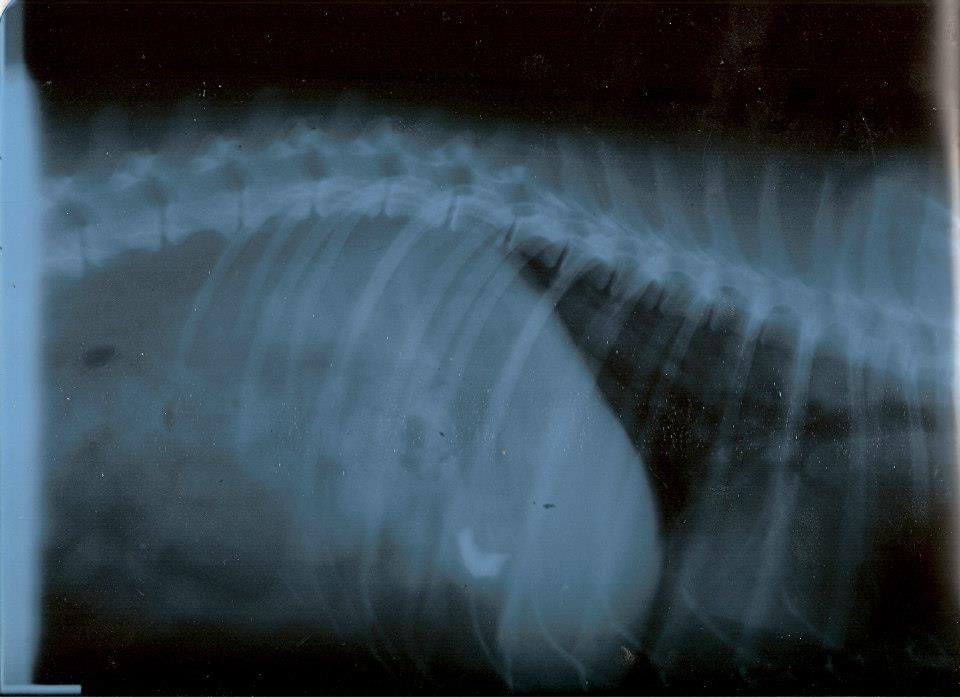

Ciao Mandy: dagli rx posso dirti al 99% che non è tumore...non li vedo...ed hai fatto stra bene a mandarmi le due proiezioni.

A questo punto però dovrei farti io alcune domande: 1) Difficoltà a respirare hai detto: fa fatica ad inspirare o ad espirare? 2) tossisce? 3) Hanno rilevato soffi cardiaci? Io, visto che dici essere peggiorato negli ultimi mesi, inserirei nella terapia (non vorrei però passare sopra i medici che lo stanno curando, quindi il mio è un consiglio nel massimo rispetto di colore sono li col cane, non potendolo io vedere) un diuretico. Il quadro polmonare mi sembra ascrivibile ad un edema polmonare. Quindi in tal caso darei Lasix o Diuren alla dose di 2 cpr ogni 12 ore. Questo lo darei anche senza avere le 3 risposte alle domande di cui sopra. Il profilo cardiaco mi sembra aumentato di dimensione..... Fammi sapere!!! I morti li portano via freddi.

Ho letto ora i tuoi commenti alle foto.....ero concentrato sulle radiografie.

Bene allora.....ma se ripeggiora, il diuretico lo darei lo stesso. Se l'animale mangia non ha effetti collaterali.... I morti li portano via freddi.

Non ti è arrivata la mail? Infatti mi sembrava strano che non mi avessi risposto. Te la incollo qui. 1. Entrambi 2. No 3. No Martedì sera gli hanno fatto una puntura di analgesico e una di un anti infiammatorio e con quelle è passato il peggio. Sembrava che stesse annegando. Siccome nella lastra si intravede un pezzo di osso nello stomaco pensano adesso che avesse avuto un gran dolore allo stomaco e respirava male per quello. Adesso sta bene il piccolo highlander. Aggiungo il diuren? |